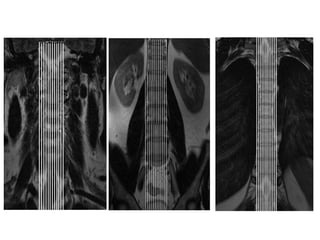

COLUNA

TORÁCICA

PROTOCOLO